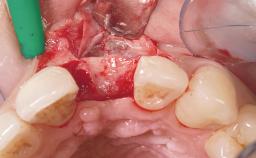

Late Placement of an Implant in a Maxillary Left Central Incisor Site

A 36-year-old female patient was referred for the replacement of the upper left central incisor (tooth 21), which had fractured. Although the tooth had been asymptomatic for many years, the crown began to loosen, at which time she presented to her dentist for an assessment. Teeth 21 and 22 had both been endodontically treated many years previously. She was a healthy individual and a non-smoker.

The crown of tooth 21 was splinted to the adjacent teeth with composite resin, and the gingiva was inflamed.

Soft Tissue Grafting Simultaneous